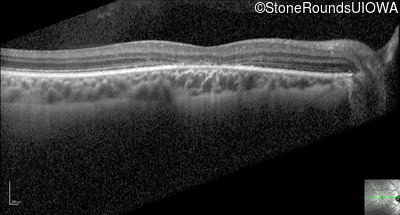

Optical Coherence Tomography - Right - 20/50 -1

Exemplar / OCT Stack

Optical Coherence Tomography - Right - 20/40 -2